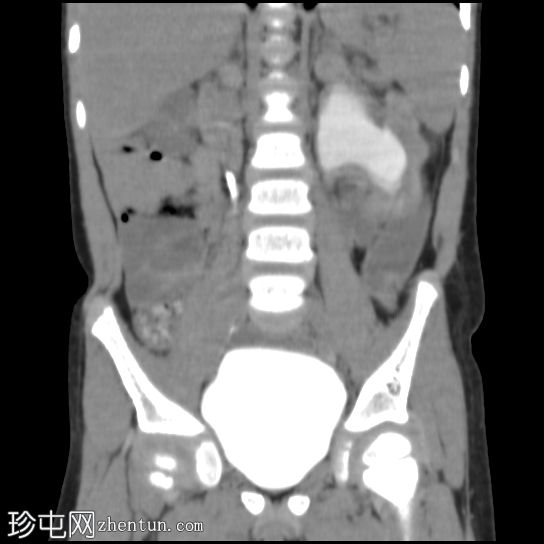

肾冠状位

排泄期

左侧肾盂肾盏系统中度扩张;但未见明确的放射性结石。

右肾未见异常。

影像

学表现最可能为左侧肾盂输尿管连接部梗阻。